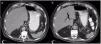

We present herein the case of a patient with gastric pneumatosis and portal vein gas that was treated conservatively. A 76-year-old man was diagnosed with high blood pressure and chronic kidney disease. He was admitted to the intensive care unit due to community-acquired pneumonia and acute respiratory failure. Nasogastric feeding was begun. Four days later, he presented with abdominal distension and diarrhea. An abdominal x-ray revealed dilation of the gastric chamber, with no dilation of the intestinal segments. An abdominal CAT scan identified pneumatosis in the distal third of the esophagus and the stomach and gas in the left portal vein (fig. 1). Angiotomography showed vascular structure permeability. Enteral feeding was suspended for one day, and then resumed, with no abdominal distension. A control CAT scan performed 5 days later demonstrated reduced gas in the portal vein and absence of gastric pneumatosis (fig. 2). The patient's pneumonia progressed, requiring mechanical ventilation, as well as kidney replacement therapy, and he died 7 days after the diagnosis of pneumatosis.

CAT is the diagnostic study of choice. Some of the findings related to GP are portal vein gas, intestinal pneumatosis, or pneumoperitoneum, and are present in 41% of the cases of EG and 33% of the cases of GE.3 Gastric mucosa ischemia may be present in half of the patients with EG that undergo endoscopy.4 Initial treatment for both entities is fluid resuscitation, fasting, gastric decompression, and broad-spectrum antibiotics, in case of signs of infection.3 Endoscopy should be performed, and if ischemia of the mucosa is documented, surgical treatment should be considered.